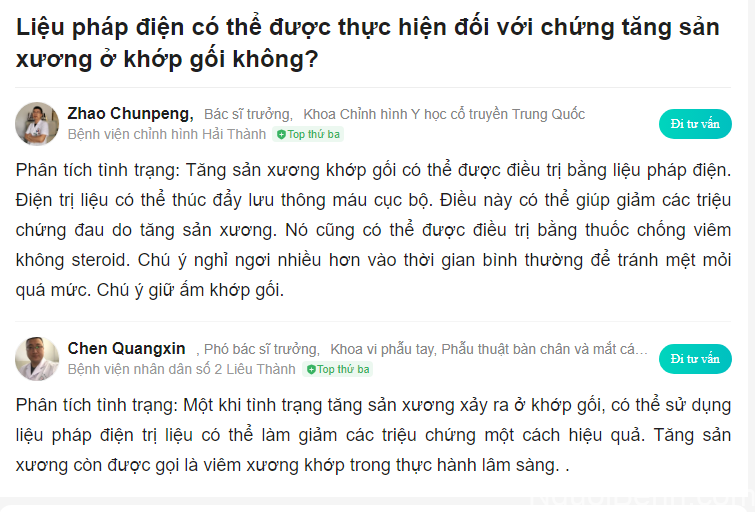

5.6. Chia sẻ từ Bác sĩ Zhao Chunpeng và Bác sĩ Chen Quangxin – Điều trị chứng loạn sản sụn xương bằng điện trị liệu

Trả lời cho câu hỏi của bệnh nhân về việc sử dụng điện trị liệu để điều trị chứng loạn sản sụn xương, cả 2 vị bác sĩ:

- Bác sĩ Zhao Chunpeng – Trưởng Khoa Chỉnh hình Y học cổ truyền Trung Quốc, Bệnh viện chỉnh hình Hải Thành

- Bác sĩ Chen Quangxin – Phó Trưởng khoa vi phẫu tay, phẫu thuật bàn chân và mắt cá chân, Bệnh viện nhân dân số 2 Liêu Thành đã chia sẻ như sau:

Chia sẻ từ Bác sĩ Zhao Chunpeng & Bác sĩ Chen Quangxin về liệu pháp điện trị liệu đối với chứng loạn sản xụn xương (GG dịch tự động)